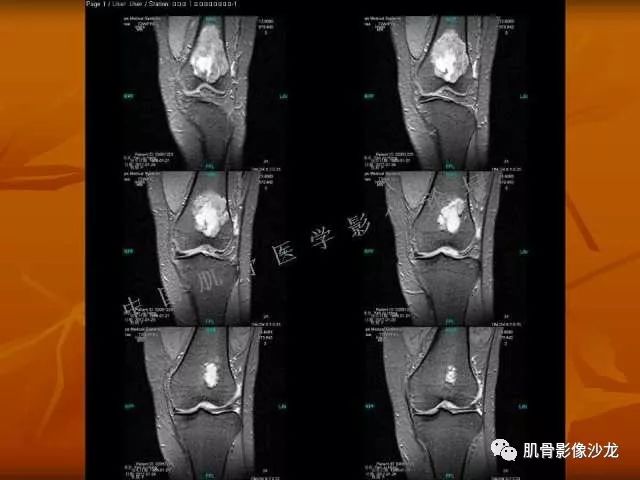

西门吹雪 :股骨下段,偏侧破坏,长T1混杂T2,移行带较窄,但局部边缘欠规则。周围骨髓水肿不明显,软组织结构清晰,T2病变上部片状低信号 , 膨胀不明显。

阳光明媚 :股骨远端前部可见片状长T1、长T2不均信号影,压脂序列呈不均高信号影,平片无明显钙化,边界清。内有纤维、粘液,

雪舞 : 股骨下端,皮质下偏心性溶骨性破坏,分叶状,T2混杂高信号。无明显软组织肿块。X片未见异常。

雪舞 第一例位置典型,但是限于资料原因,未能明确是否有钙化,周围也未见软组织肿块,骨膜反应

雪舞 :不过T2高信号,分叶状还是要想到软骨肉瘤,毕竟典型位置,骨肿瘤排名第3的软骨肉瘤